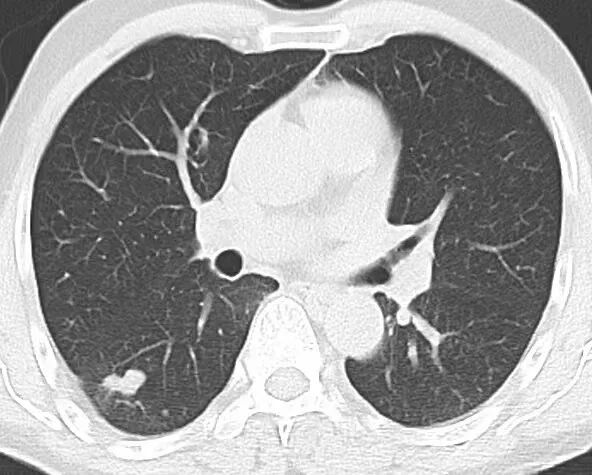

68 岁的刁老先生来自江苏扬州,一月前在一家医院体检时,一份右肺下叶结节的 CT 报告让他的生活泛起了涟漪。报告显示,右肺下叶存在实性结节,大小约 17mm×10mm,影像学可见毛刺、胸膜牵拉及分叶征等高危特征,初步判断为恶性肿瘤可能,建议进一步穿刺活检。看到报告的瞬间,刁先生的脑海中浮现出一个名字——西安市人民医院航天院区胸部病院副院长张潍主任医师。出于对张潍教授的深切信任,刁老先生与家属毅然决定专程前来就诊,并表达了希望进行手术治疗的意愿。